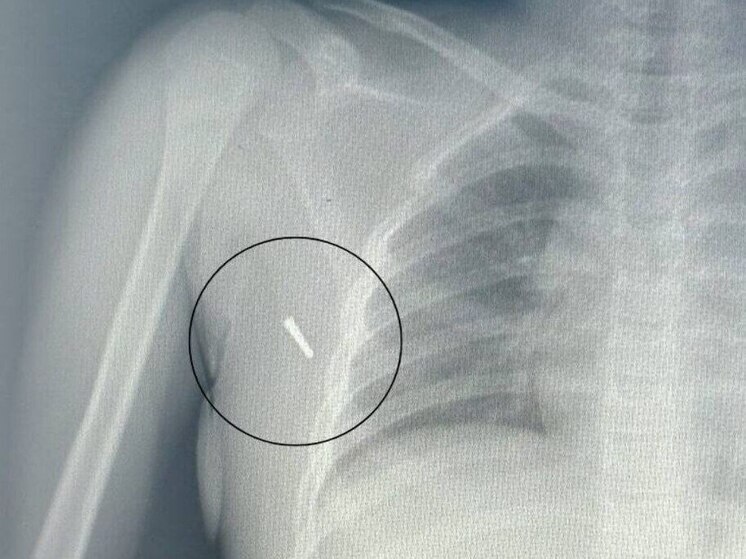

Врачи Артемовской городской больницы спасли жизнь восьмилетней девочке, в тело которой в результате ДТП проник наконечник ртутного термометра. Об этом сообщили в медицинском учреждении.

Инцидент произошел 18 июля. По данным медиков, ребенок ехал в автомобиле с установленным в подмышку градусником – в это время транспортное средство попало в дорожно-транспортное происшествие. От удара наконечник градусника отломился и глубоко проник в мягкие ткани подмышечной впадины.

«Ситуация была крайне неординарной. Мы имели дело не просто с механическим повреждением, но с потенциальной угрозой отравления парами ртути. Девочка поступила в приемное отделение в сопровождении родителей, травматологи немедленно приняли решение об извлечении инородного тела», – рассказали в приемном покое стационара.

Операция по извлечению наконечника прошла успешно. Медики провели полный комплекс обследований – включая рентген и анализы на наличие интоксикации. После вмешательства девочка осталась под наблюдением в стационаре.